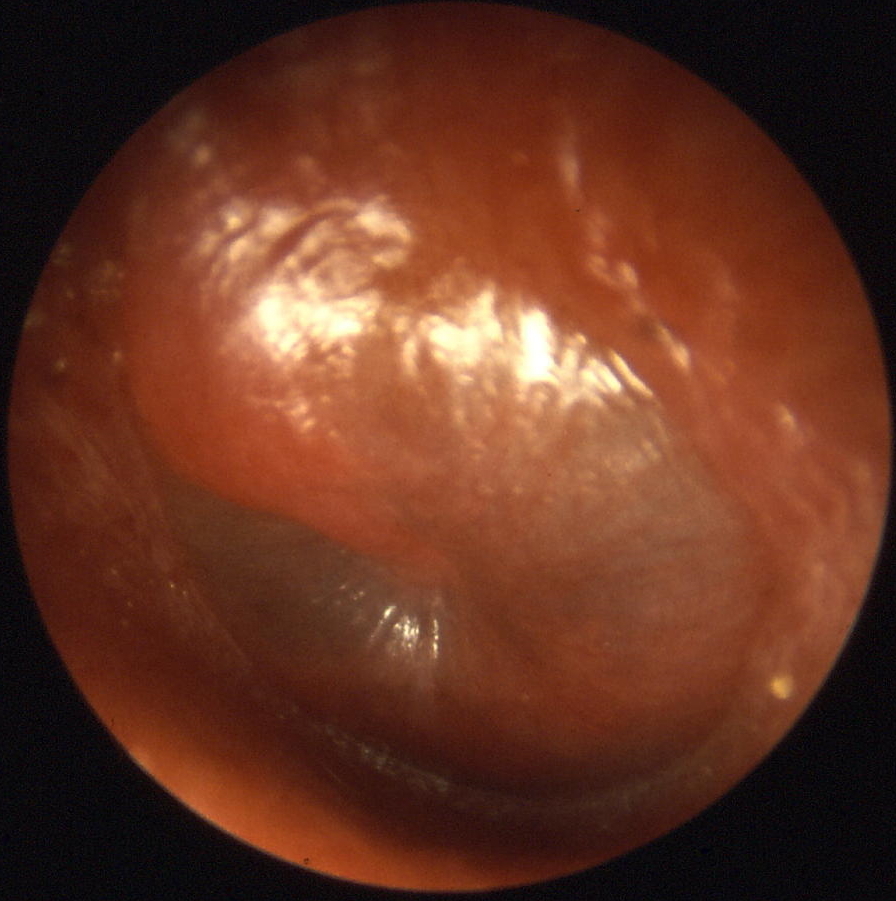

2. Middle Ear Infection (Otitis Media)

Common in children. Symptoms: earache, fever, hearing difficulty, sometimes fluid behind the eardrum.